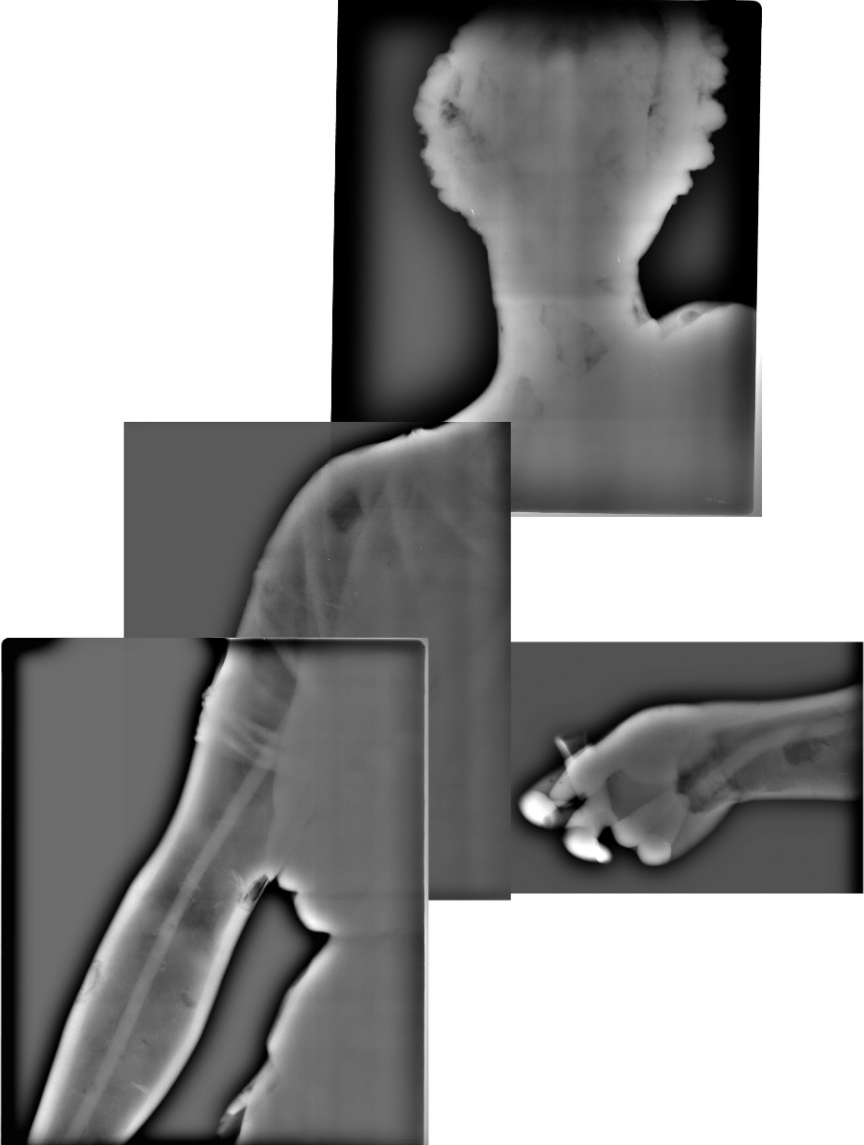

Le principe de la scintigraphie (figure 2.13) est de détecter des radiotraceurs spécifiques préalablement injectés dans l’organisme humain qui vont se fixer sur les organes à examiner sans perturber les processus métaboliques. On peut ensuite visualiser le fonctionnement de l’organe à traiter (ou à étudier) en suivant le trajet du radioélément dans le corps (thyroïde avec l’iode, os avec le technétium 99m24 qui a la propriété de s’y fixer, etc.).

Figure 2.13 – Scintigraphie. (a) Gamma caméra à scintigraphie. Cet appareil fait l’imagerie des photons \(\gamma \). Source : Wikipédia/Brendaicm. CC BY-SA. (b) Résultat d’une scintigraphie osseuse : on injecte au patient du technicium 99m qui est radioactif \(\gamma \) et qui a la particularité de se fixer sur les os. L’image de ce patient montre l’intensité de l’émission \(\gamma \) que les médecins interprètent comme des métastases osseuses. CC0.